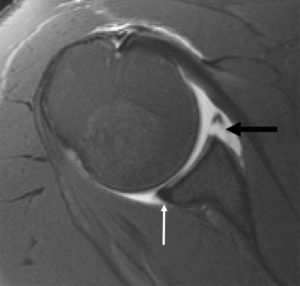

Bankart Lesion is an MRI Finding. It results from detachment of the anterior inferior labrum from the underlying glenoid, and is usually as a result of previous Anterior Shoulder Dislocation.

The detachment may be labral (Soft Tissue) only, or may involve the bony margin of the glenoid (impaction fracture) called the Bony Bankart. Additionally, labral tears may also be present.